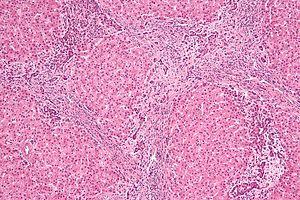

Focal nodular hyperplasia - intermed mag.jpg

Micrograph of focal nodular hyperplasia. H&E stain.

Focal nodular hyperplasia's most recognizable gross feature is a central stellate scar seen in 60–70% of cases. Microscopically, a lobular proliferation of bland-appearing hepatocytes with a bile ductular proliferation and malformed vessels within the fibrous scar is the most common pattern. Other patterns include telangiectatic, hyperplastic-adenomatous, and lesions with focal large-cell dysplasia.[2] Rarely, these lesions may be multiple or can occur as part of a syndrome with hemangiomas, epithelioid hemangioendothelioma, hepatic adenomas, fibrolamellar hepatocellular carcinoma, vascular malformations of the brain, meningiomas, and/or astrocytomas.[2]